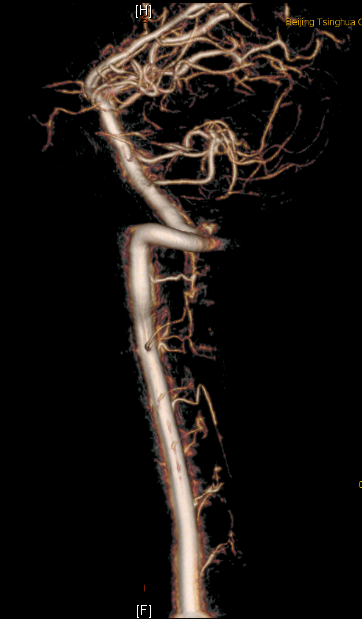

图2:术前DSA正侧位显示延髓至颈3水平畸形血管团

图3:术后复查显示切除畸形血管团后 (对比图2)